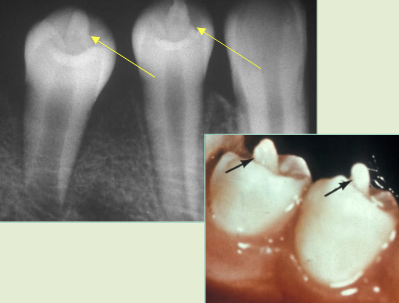

deep surface enamel invagination of the crown or root “tooth within tooth”; can be coronal (most frequent) or radicular

dens invaginatus “dens in dente”

“dens in dente” type I

invagination is confined to the crown

“dens in dente” type II

invagination extends below the CEJ

“dens in dente” type III

invagination may extend through the root

what is the dx?

dense invaginatus